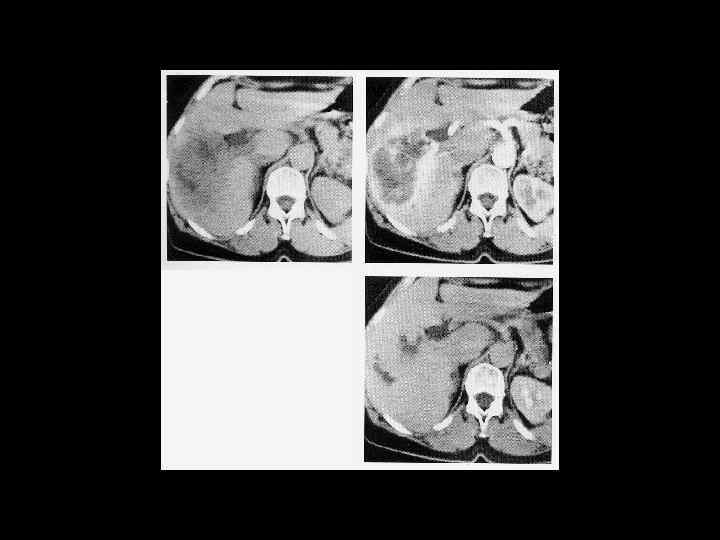

АКТУАЛЬНЫЕ ВОПРОСЫ РЕНТГЕНОЛОГИИ ЛУЧЕВАЯ ДИАГНОСТИКА ОЧАГОВЫХ ПОРАЖЕНИЙ ПЕЧЕНИ МЕТАСТАТИЧЕСКОЕ ПОРАЖЕНИЕ ПЕЧЕНИ Компьютерно-томографическая семиотика: - образования имеющие как правило низкую плотность (30 -50 ед Н), которая мало изменяется или вовсе не изменяется после введения РКВ (наибольшее усиление дают метастазы гипернефромы)

АКТУАЛЬНЫЕ ВОПРОСЫ РЕНТГЕНОЛОГИИ ЛУЧЕВАЯ ДИАГНОСТИКА ОЧАГОВЫХ ПОРАЖЕНИЙ ПЕЧЕНИ Диагностическая информативность КТ в выявлении метастатического поражения печени Чувствительность Специфичность Точность 85 -90%

АКТУАЛЬНЫЕ ВОПРОСЫ РЕНТГЕНОЛОГИИ ЛУЧЕВАЯ ДИАГНОСТИКА ОЧАГОВЫХ ПОРАЖЕНИЙ ПЕЧЕНИ МЕТАСТАТИЧЕСКОЕ ПОРАЖЕНИЕ ПЕЧЕНИ МР семиотика: Т 1 взвешенные изображения - множественные участки со слабым сигналом Т 2 взвешенные изображения - яркий сигнал от метастазов